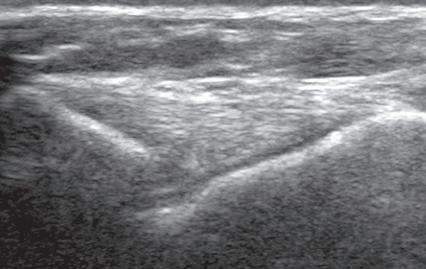

labrum of the hip and shoulder, and the knee menisci are hyperechoic (Fig. 1.7B). Ligaments have a hyperechoic, striated appearance that is more compact compared with tendons (Fig. 1.8). In addition, ligaments are also identified in that they connect two osseous structures. Often normal ligaments may appear relatively hypoechoic when surrounded by hyperechoic subcutaneous fat; however, a compact linear hyperechoic ligament can be appreciated when imaged in long axis perpendicular to the ultrasound beam. Normal peripheral nerves have a fascicular appearance in which the individual nerve fascicles are hypoechoic, surrounded by hyperechoic connective tissue epineurium (Fig. 1.9).4 Hyperechoic fat is typically seen around larger peripheral nerves.

FIGURE 1.8 Tibial Collateral Ligament. Ultrasound image of tibial collateral ligament of the knee in long axis shows compact fibrillar echotexture (arrowheads). F, Femur; m, meniscus; T, tibia.